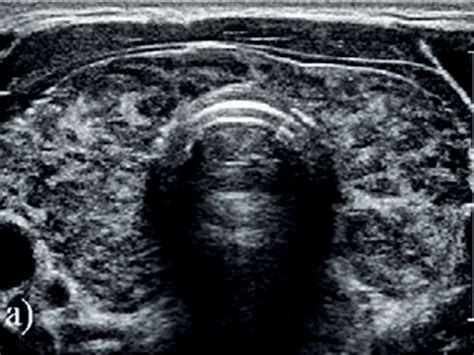

Si se palpan nódulos en la glándula, se puede indicar una ecografía tiroidea para obtener una imagen detallada. Los análisis de sangre son cruciales para evaluar la función tiroidea, midiendo los niveles de hormona estimulante del tiroides (TSH) y tiroxina (T4). Si se sospecha hipertiroidismo, también se mide la concentración de triyodotironina (T3).